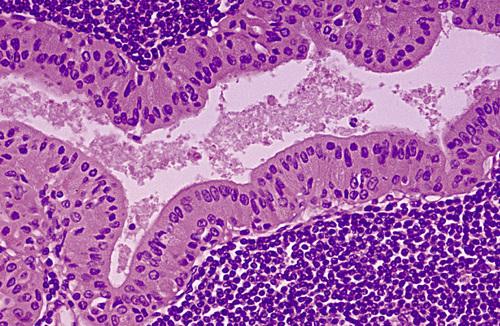

High-power view of epithelial lining showing double row of oncocytes with adjacent lymphoid stroma. The inner luminal layer consists of tall columnar cells with centrally placed, palisaded, and slightly hyperchromatic nuclei. Beneath this is a second layer of cuboidal or polygonal cells with more vesicular nuclei.

Warthin tumor